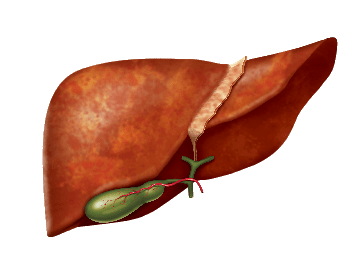

Найбільш важливі функції печінки пов'язані з

роботою гепатоцитів - клітин печінки:

- метаболічна участь в обміні білків, жирів, вуглеводів, вітамінів, мікроелементів, гормонів

- захисна руйнування біологічно активних агентів

- знешкоджує знешкодження токсичних речовин

- секреторна екзокринна - утворення і виділення жовчі, ендокринна - виділення в кров синтезованих або метаболізованих продуктів

Що робити при виявленні проблем з печінкою?

Основні підходи

до лікування захворювань печінки

- Усунення причини захворювання

- ліквідація запального процесу в печінці

- Відновлення пошкоджених гепатоцитів